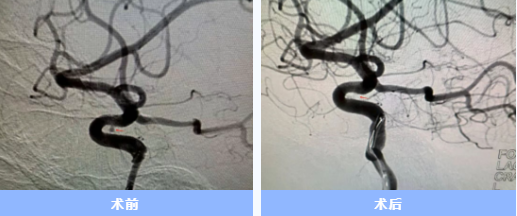

入院后急診完成了頭頸部血管檢查,卻未發(fā)現(xiàn)動(dòng)脈瘤。神經(jīng)內(nèi)科一病區(qū)負(fù)責(zé)人胡蘇華當(dāng)晚緊急為患者做了更精確的腦血管造影,終于發(fā)現(xiàn)右側(cè)頸內(nèi)動(dòng)脈上藏著一個(gè)極其微小的動(dòng)脈瘤——直徑僅約1毫米左右,堪稱從醫(yī)二十多年來遇見的最難發(fā)現(xiàn)的"炸彈"。

手術(shù)當(dāng)天,胡蘇華與主治醫(yī)師陳浩協(xié)作,首先經(jīng)患者右手橈動(dòng)脈成功建立治療通道,隨后才實(shí)施全身麻醉,以最大限度縮短麻醉時(shí)間。憑借精湛技藝,團(tuán)隊(duì)迅速而完整地栓塞了動(dòng)脈瘤。術(shù)后患者很快在ICU蘇醒,四肢活動(dòng)良好,第二天即返回普通病房。